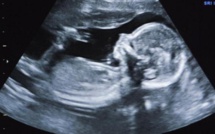

Chili: une femme de 92 ans porteuse d'un foetus momifié 20/06/2015

Santiago du Chili, Chili | AFP | samedi 20/06/2015 - Des examens de routine après une chute ont révélé qu'une grand-mère chilienne de 92 ans portait...